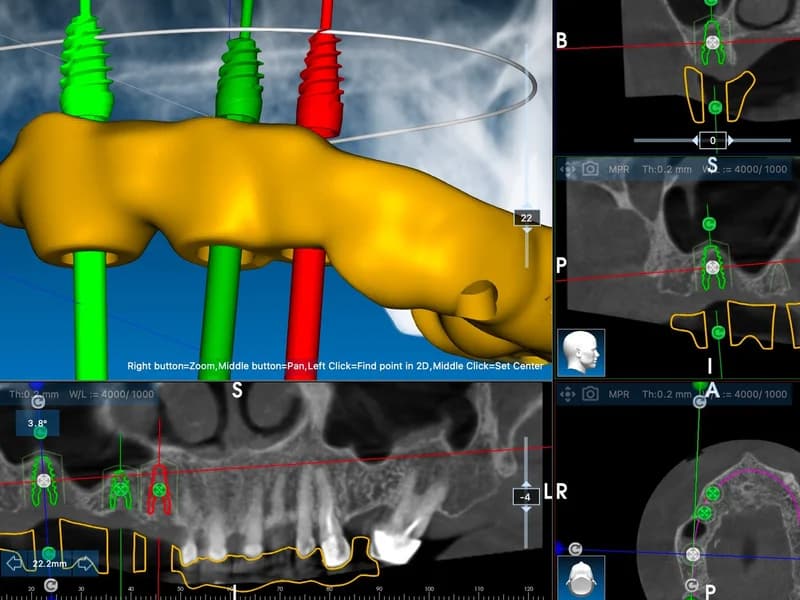

- –CBCT snimanje zubi(Najprecizniji oblik dentalnog snimanja koji omogućuje trodimenzionalni prikaz zuba, kosti i okolnih struktura. Koristi se najnovija digitalna CBCT tehnologija s niskom dozom zračenja i iznimnom rezolucijom. Precizan prikaz do 0,01 mm, veliko polje snimanja (do max. 20x17 cm).)